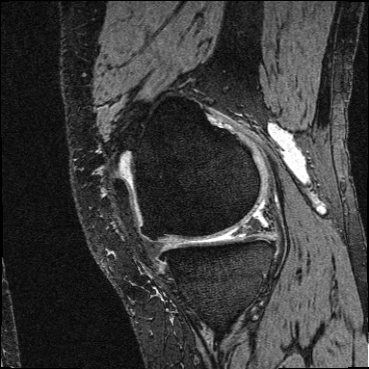

OAI Knee MRI We train and test on the split published with [22], with 2532 training examples and 301 test pairs from the Osteoarthritis Initiative (OAI) [16]444https://nda.nih.gov/oai. We evaluate using the mean Dice score of tibial and fibial cartilage. To compare directly to [22, 7, 23] we train and evaluate at [80x192x192].

| Moving Image | Warped Image | Fixed Image | Moving Image | Warped Image | Fixed Image |